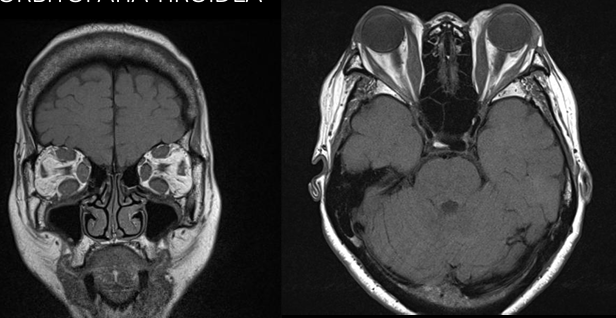

13

Q

RM en retinoblastoma

A

Evaluar implicaciones intra y extraoculares / intracraneales

Hemorragia retinal

15

Dx desprendimiento de retina

Fondoscopia

US/TC

RM - evaluar presencia neoplasias